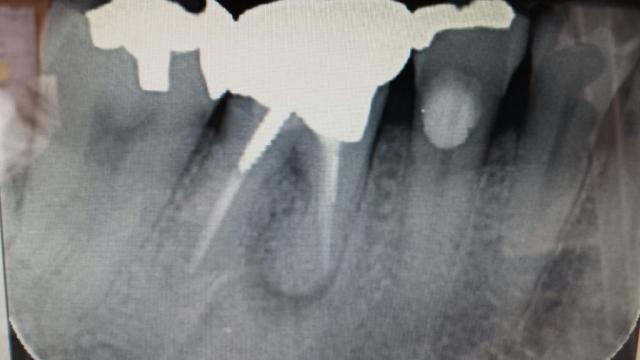

今日の

根

管治療

初回ではクラウン、メタルコア、ゲーツドリルで

管口を広げて、

管充填剤の除去で終わる。

2回目で#10Kファイルでひたすら

尖部を目指しEDTAでスメア層の除去、ヒポクロで洗浄、水酸化カルシウム粉末を入れてキャビネットで仮封。

3回目で

管充填。

術前、術後(

管充填と同時にファイバーコア、形成、印象まで)